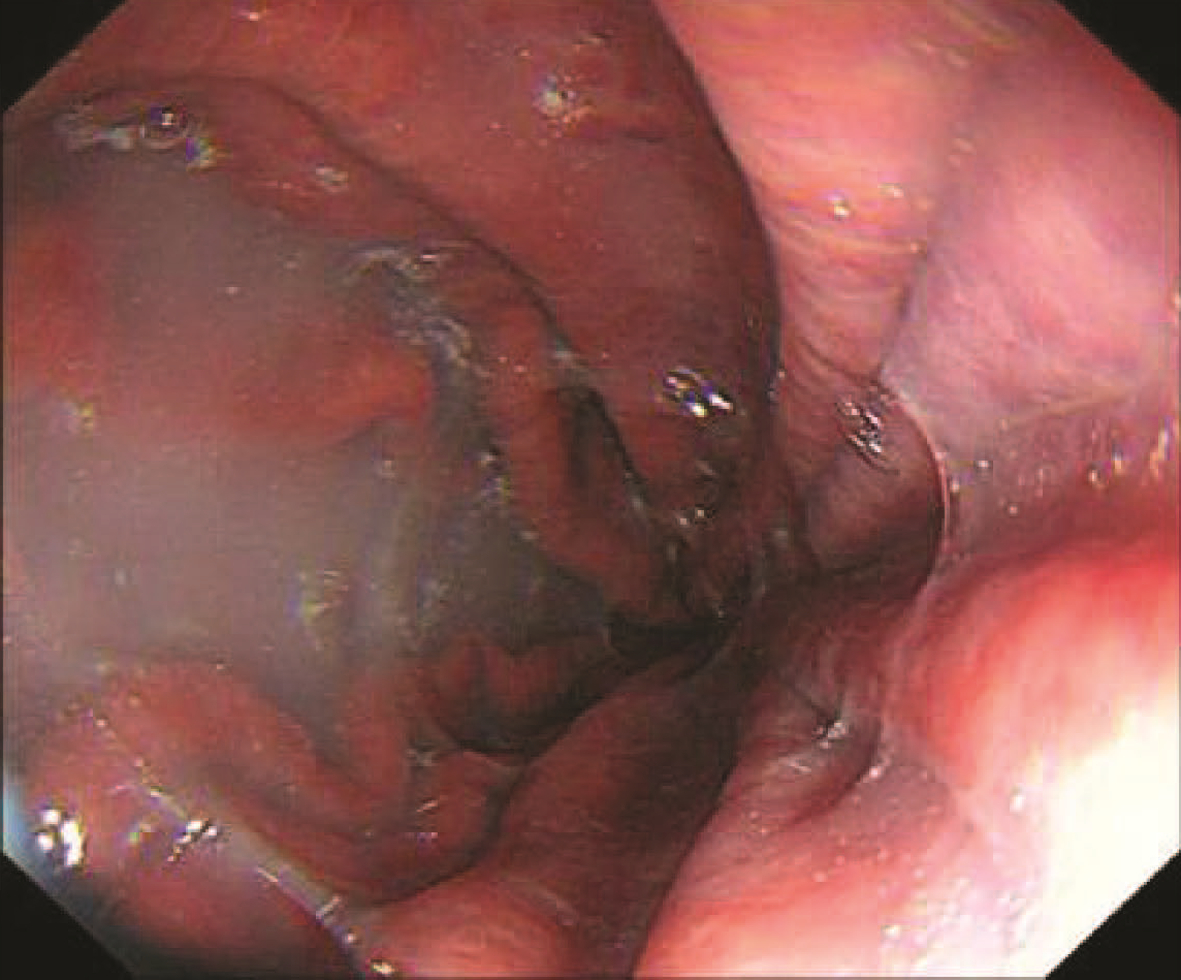

Massive hepatic hemangioma with diffuse arterioportal fistula: A case report

Figures(5)